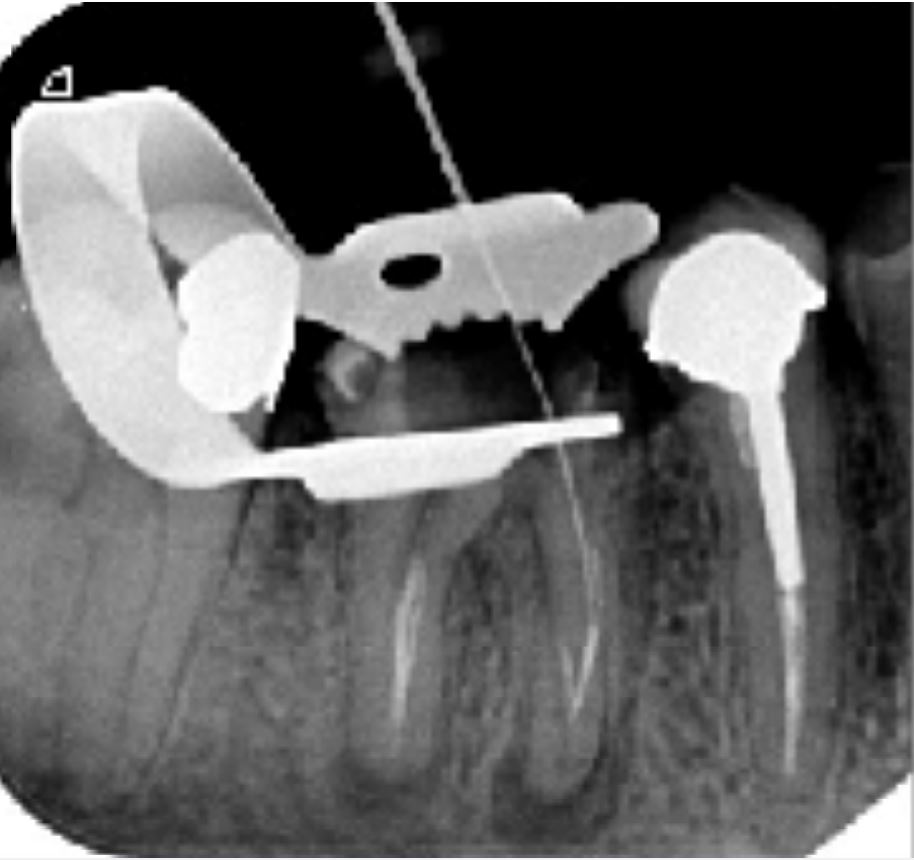

Radio Per-Opératoire

Désobturation progressive du système canalaire à l'aide de séquence FANTA RETREATMENT

Mise en évidence d'un fragment instrumental dans la racine MV de la 46

Retrait du fragment à l'aide d'inserts endodontiques

Mise en évidence de la dépose du fragment instrumental